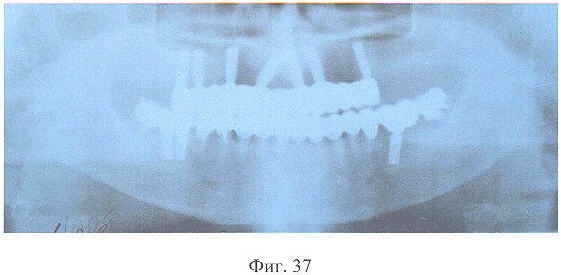

На фиг.37 – рентгенограмма больной Ч. через 3 года после зубного протезирования.

Адаптация к протезам протекала в течение 7 суток, после чего больная отмечала удовлетворительное функциональное состояние зубочелюстного аппарата. Признаков резорбции костной ткани вокруг дентальных имплантатов по данным рентгенологического исследования через 3 года после зубного протезирования не выявлено, больная жалоб не предъявляла, состояние протезов удовлетворительное.